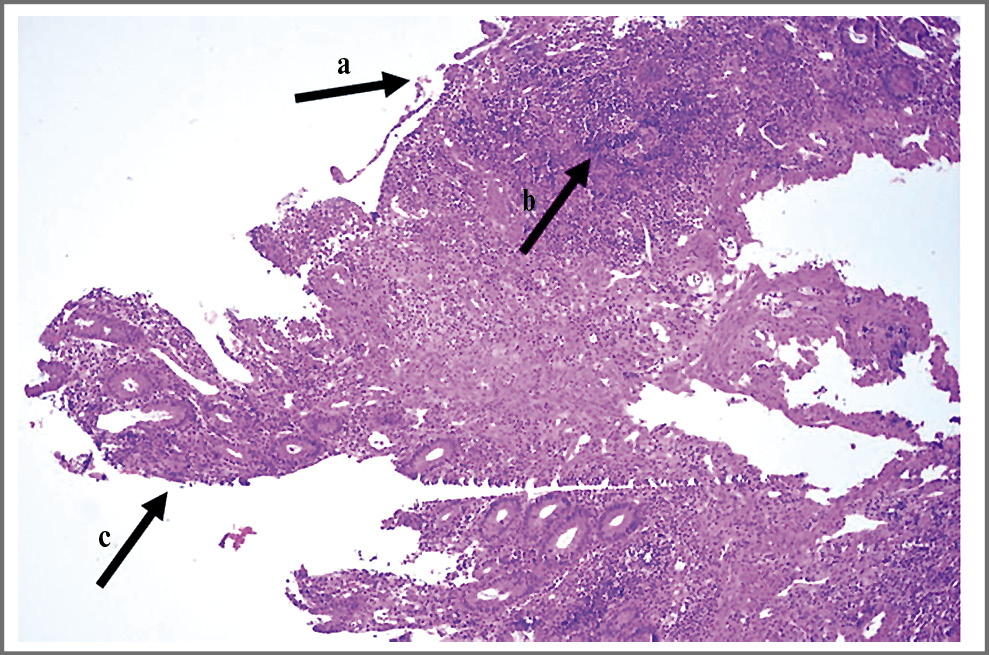

Рис. 1. Фрагмент слизистой оболочки толстой кишки с очаговым некрозом поверхностного эпителия. Покровный эпителий частично представлен незрелыми регенерирующими эпителиоцитами, лишенными муцина (a). Плотный инфильтрат, состоящий из лимфоцитов и плазматических клеток, нейтрофильных лейкоцитов в пределах слизистой оболочки (b) и поверхностных отделах подслизистого слоя; наличие небольших эрозий меду криптами (c). Железы с кистозным расширением (d) и наличием в просвете гомогенного содержимого с примесью лейкоцитов; формирование крипт-абсцессов. Окраска гематоксилином и эозином ×200.